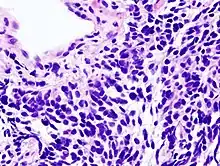

O câncer de pulmão é classificado de acordo com o tipo histológico.[50] Essa classificação tem implicações importantes no manejo clínico e no prognóstico da doença. A vasta maioria dos tumores de pulmão é do tipo carcinoma - doença maligna derivada de células epiteliais. Os carcinomas de pulmão são categorizados pelo tamanho e aparência das células malignas observadas no tecido de biópsia por um patologista em um microscópio. As duas classes gerais são carcinomas não pequenas células e pequenas células.[51]

No carcinoma de pulmão pequenas células (CPC), as células contêm densos grânulos neurossecretores (vesículas contendo hormônios neuroendócrinos), que conferem a esse tumor uma associação com a síndrome endócrina/paraneoplásica.[54] A maior parte dos casos surge nas grandes vias aéreas (brônquios primários e secundários).[9] Esses tumores crescem rapidamente e se espalham precocemente no curso da doença. 60–70% dos pacientes já possuem doença metastática à apresentação. Esse tipo de câncer de pulmão está fortemente associado ao tabagismo.[7]